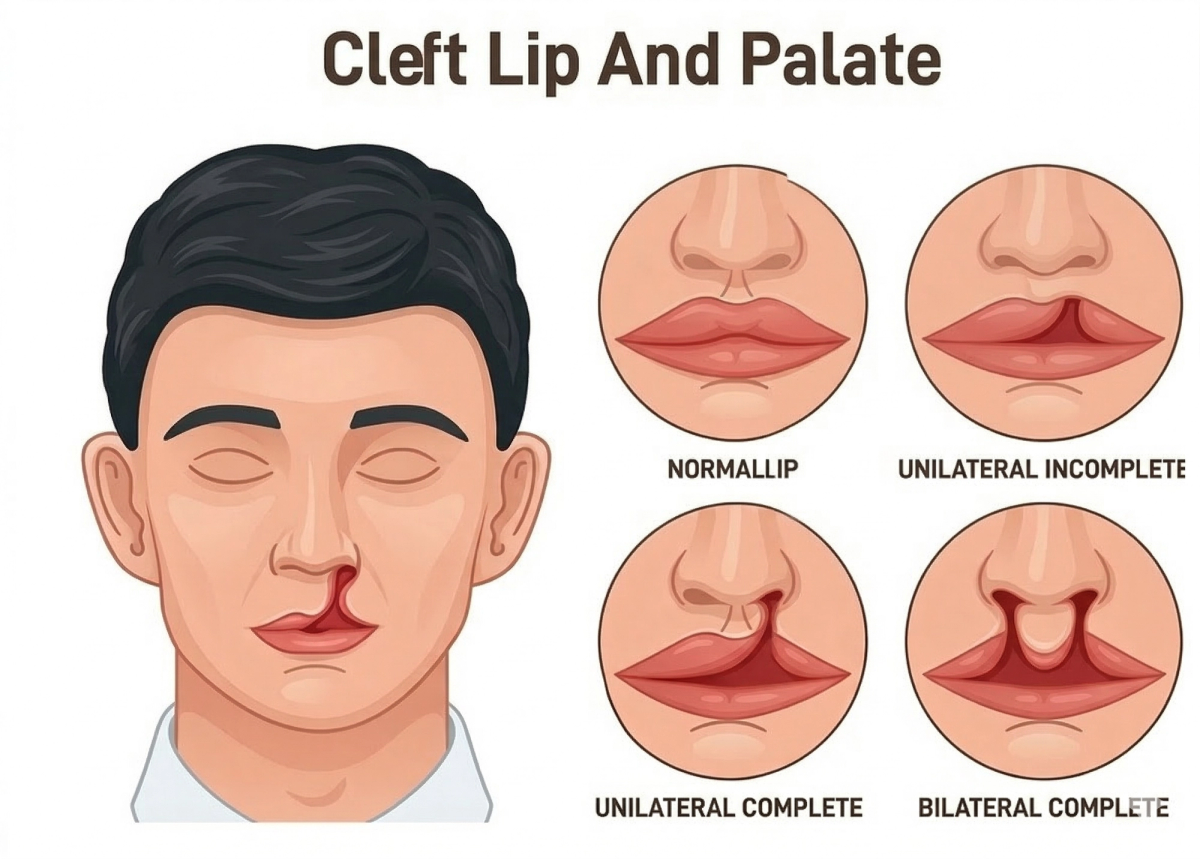

Cleft Lip & Cleft Palate Treatment

Treatment for patients of all ages